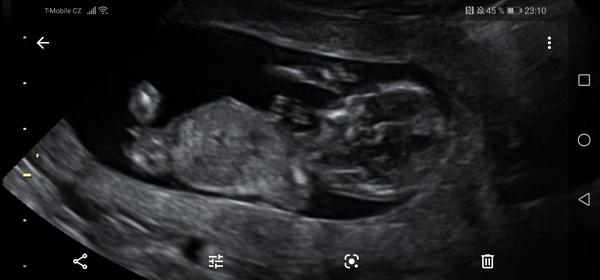

@kajda3 mám ještě tyhle. Ta jedna jsou vyloženě nožičky a bříško, je jakoby cele k nám.

@kajda3 ještě možná tuhle, tady přirození trochu je vidět, po přiblížení. Prý ty pysky jsou taky hodně velké. Prostě nevím. 😥